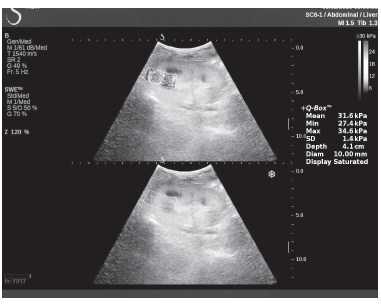

Клинический пример из первой группы. Пациент М., с хронической почечной недостаточностью. Трансплантация почки произведена от живого родственного донора. Трансплантат находится в правой подвздошной области. При нормальном функциональном состоянии трансплантата, показатели цветовой и спектральной допплерографии оценивались как удовлетворительные, с индексом резистентности не более 0,60 (рис. 1); показатели жесткости паренхимы почечного трансплантата при УЭСВ на различных участках составили от 20,05 до 29,18 кПа (рис. 2-4).

Рисунок 4. Исследование в режиме ультразвуковой эластографии сдвиговой волны у пациента М.: жесткость паренхимы в зоне нижнего полюса почечного трансплантата 16,8 кПа

Рисунок 9. Исследование в режиме ультразвуковой эластографии сдвиговой волны у пациента К.: жесткость паренхимы у верхнего полюса почечного трансплантата 31,6 кПа